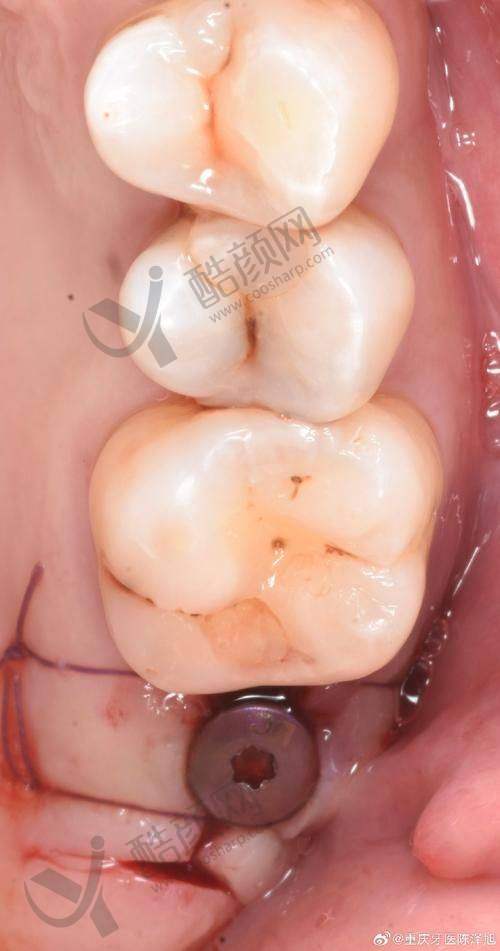

实例二:张女士因意外导致牙齿脱落,希望能够尽快修复牙齿的美观和功能。陈丹军主事为她采用了微创种植技术,手术过程中几乎没有出血,张女士也没有感到明显的疼痛。术后,张女士对种植成效非常满意,称赞陈主事技术高超。